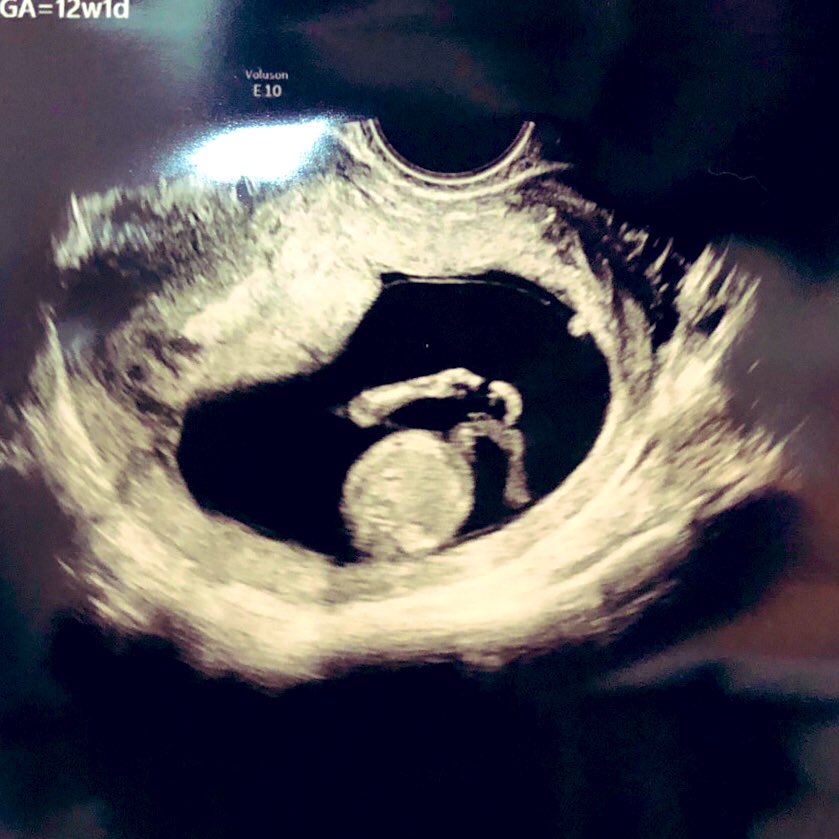

12w1d 胎児ドック+NIPT

雪の中、愛育クリニックへ❄️

初期精密経腹エコーで

30分じっくり診ていただき、

元気な姿を見れて嬉しい☺️

性別はほぼ確定

ジンクス当たらなかった‥!

何でも嬉しい

NIPTのカウンセリングはあっさり終了

そして採血

金額は14万円ほど

待ち時間はなし

あとは結果待ち‥🙏 2022-02-10 19:42:00